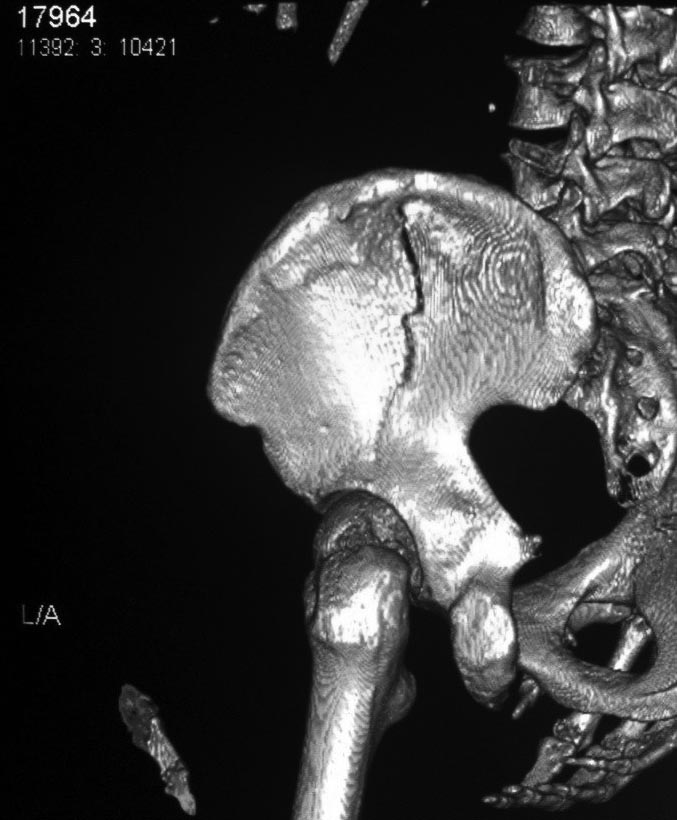

Это высокий перелом передней колонны вертлужной впадины (62A3.2).

Появились новые проекции. Да, это высокий перелом передней колонны левой вертлужной впадины со смещением.

А есть другие проекции? Нет ли там поперечного перелома задней колонны?

Да, я понимаю, что предпочтительнее всего накостный синтез. Но если сравнивать АВФ с миниинвазивным, то ни тот ни другой не гарантируют 100%й репозиции. Перелом начинается с передней стенки впадины, идет вверх до крыла, а сзади спускаясь, останавливается едва достигнув задней колонны. Да, задняя колонна цела. Есть поперечные срезы КТ (сейчас показать не могу), где это четко видно. Перелом не завершенный. Учитывая этот факт, я и подумал о возможности АВФ. Простите мне мою упрямость)).

Относительно диагноза соглашусь с коллегами повреждение крыла и передней колоны вертлужной впадины ближе к типу В по классификации Летурнеля, хотя не в полной мере ей соответствует. Согласно Матта смещение более 3х мм -показание к открытому остеосинтезу, в данном случае скорее из илиоингвинального доступа или Стоппа. Хотелось бы конечно увидеть остальные срезы и рентгенограммы.

В последнее время, из-за красоты участился показ 3D снимков, хотя надо начать c обычных, и, по необходимости, компьютерная томография с 3D! Без головки бедра 3D покажет общую картину и вовлечение сустава, а более детально только в срезах КТ.

Данная картина показывает очень редкий перелом передней колонны, но перед операцией еще раз надо просмотреть обещанные дополнительные КТ срезы.